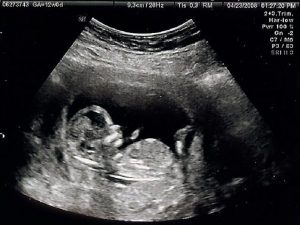

1. 超聲檢查

超聲心動圖是在超聲或超聲波的幫助下獲得心臟醫(yī)學圖像的過程。它允許醫(yī)生通過將心臟暴露于超聲波并檢測在撞擊心臟壁或心室后反射回來的波來獲得心臟的移動或?qū)崟r圖像。超聲心動圖的過程是無痛和安全的。